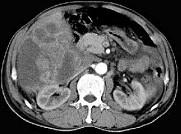

问题 男,62岁,右上腹痛半年,腹部包块,黄疸较重,AFP阴性,CT检查如图,最可能的诊断为()

选项 A.原发性肝癌 B.胆管上皮癌 C.肝囊肿 D.肝脓肿 E.肝错构瘤

答案 B